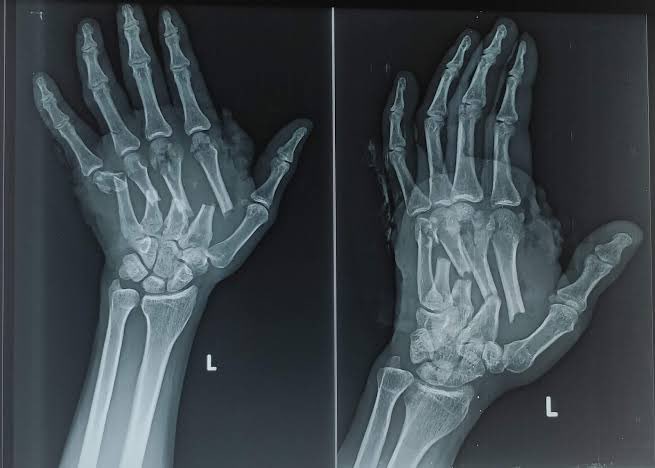

متلازمة الهرس " توعوي مهم "‼️

إذا لا سمح الله حصل حادث ما كإنهيار مبنى أو حادث سيارة ، وفُقد شخص أو عدة أشخاص ممن تعرضوا للحادث تحت الأنقاض أو السيارة واستمر الضغط لفترة تصل إلى 15 دقيقة ، لا تحاول إخراج المصاب بدون حضور مسعف أو شخص مختص .

لأن هناك خطر كبير في حالة القيام بسحبه أو إزالة الضغط من فوقه

فإزالة الحطام عن العضلات المهروسة فجأة ، يجعل جسم المصاب يفرز مواد إنحلال العضلات مثل البوتاسيوم والفوسفور بكميات كبيرة مما يسبب فشل كلوي وتسمم المصاب .

المسعف سيقوم بإزالة الحطام ببطء وسيحقن المصاب ببعض المواد التي تخفف من الأضرار

يعرف هذا الأمر بمتلازمة الهرس

( Crush Syndrome)